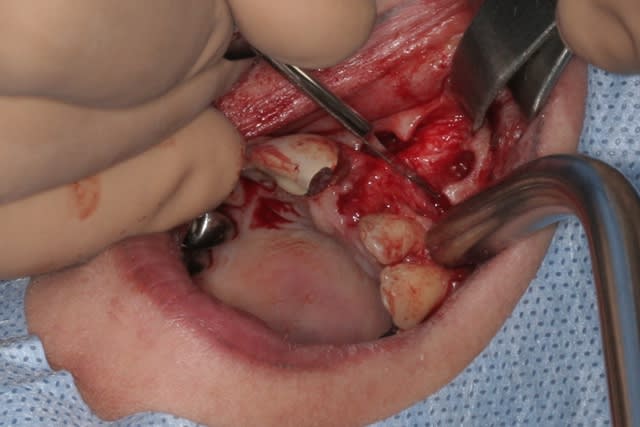

tien, ce matin, extraction de 24/25, curetage méticuleux, forage, comblement du gap, pose des 2 implants qui se sont bloqués à 50Ncm au CA sur les 3 ou 4 mm apicaux, pose des vis de cicat, sutures...35min....tranquille...

un autre cas EII MCI sur 11/21...mais en photos (j'ai aussi la vidéo, faut que je la passe sur youtube)